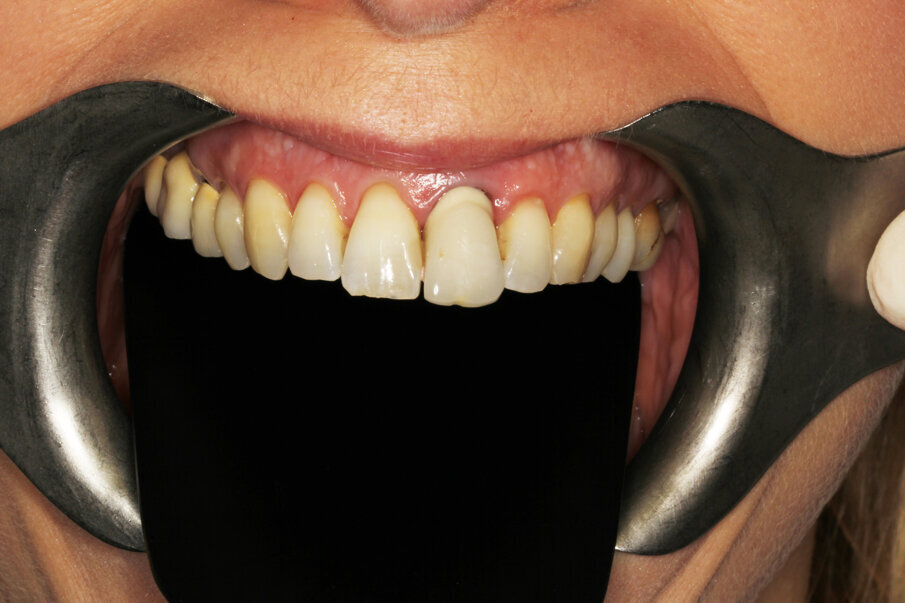

Definitive crown

The author strongly prefers screw-retained devices. Owing to the angulation of the implant, it was necessary to relocate the screw access hole. In CAD, the design for a cobalt-chromium support that copied the gingival profile of the temporary was prepared, and the screw access was brought to the palatal aspect (Fig. 37). The file was sent to the Arc solutions milling centre in Helsingborg in Sweden. High-quality material and CAM production guarantee an excellent outcome in terms of connection and smooth surfaces (Figs. 38–40). The technician layered feldspathic ceramics to obtain the final anatomy and texture. The patient was totally satisfied with the result and did not wish for intervention for the maxillary right central incisor. Minor gingival asymmetries, though evident at high magnification in photography, are not really disturbing when viewed at social distance if all other parameters, like colour, incisal edge, tooth texture, correct proportion of the incisal two-thirds of the tooth and transitions, are respected (Figs. 41–43).